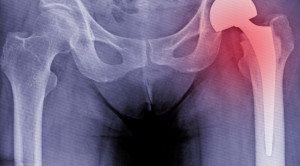

• Strategi Pencegahan Fraktur karena Osteoporosis

Strategi Pencegahan Fraktur karena Osteoporosis

Strategi pencegahan fraktur karena osteoporosis harus dipahami dan dilaksanakan, karena angka morbiditasnya yang semakin meningkat. Pasien yang telah terdiagnosis osteoporosis, agar tidak...(Baca Selengkapnya)

• Suplementasi Kalsium dan Vitamin D Terbukti Tidak Menurunkan Insidensi Fraktur Pada Lansia

Suplementasi Kalsium dan Vitamin D Terbukti Tidak Menurunkan Insidensi Fraktur Pada Lansia

Keperluan pemberian suplementasi kalsium dan vitamin D untuk mencegah fraktur pada lansia masih menuai perdebatan.[1] Suplementasi kalsium dan vitamin D sudah lama...(Baca Selengkapnya)